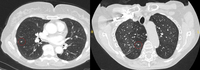

Cortes de tomografia computadorizada (TC) de dois casos com nódulos perifissurais benignos. Observe as margens lisas e a fissura adjacente normal e intacta

Do acervo de Dr. George Tsaknis, MD, PhD, FRCP (Londres), MRQA, MAcadMEd, PGCert; usado com permissão